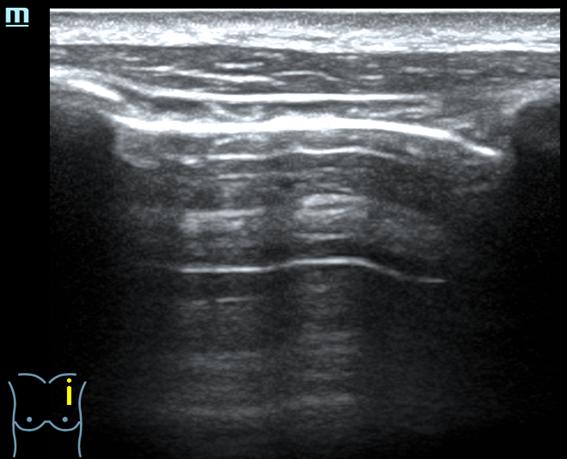

- Ecografía pulmonar (protocolo BLUE): Perfil A en los 4 puntos BLUE anteriores: deslizamiento pleural y líneas A. Signo de la playa en modo M. Puntos PLAPS: deslizamiento pleural, irregularidades pleurales, >2 líneas B.